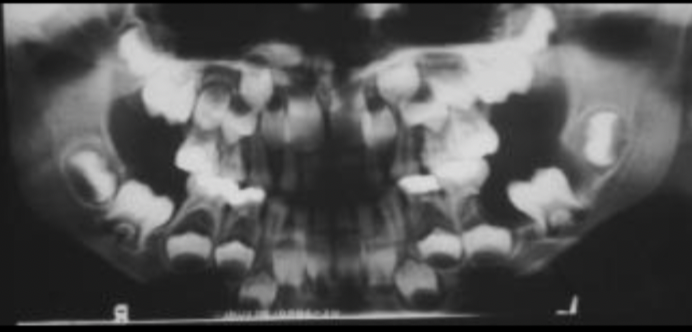

ameloblastic fibroodontoma

33

34

35